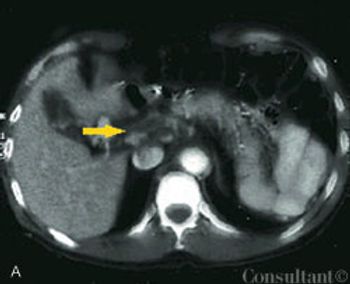

An obese 55-year-old woman had intermittent dysuria and frequent urination for 4 days and fever, abdominal pain, and vomiting for 3 days. Her history included type 1 diabetes mellitus, hypertension, and angina; her medications included insulin, nifedipine, and nitroglycerin.